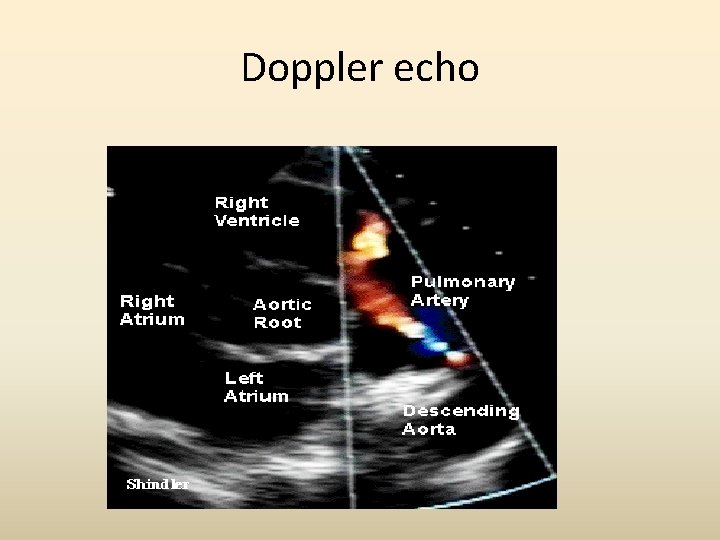

PSAX – Colour Doppler Echo -Identify the ‘central flame in the blue stream’ (red - PDA blue-LPA, RPA, Desc Ao) Ao - A flow that appears to come from the left corner of the LPA origin and directed usually towards the left PV However again confusion arises in the case of a predominant R to L shunt through the PDA.

Doppler echo